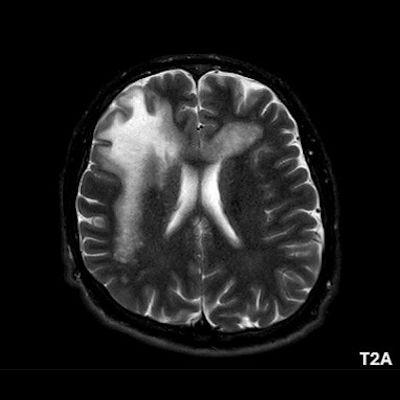

1. A) Aksiyel T2A görüntülerde bilateral sağda belirgin frontoparietal subkortikal ve derin periventriküler beyaz cevherde subkortikal U fiberleri boyunca yerleşimli sinyal artımları (oklar) izlendi.  Tarifli alanlar aksiyel T1A serilerde hipointens görünümde (oklar) izlendi.

1. PML’de MRG bulguları genellikle multifokal, asimetrik periventriküler ve subkortikal beyaz cevher tutulumu şeklindedir. Subkortikal U-fiberleri sıklıkla tutulur, özellikle parietooksipital bölgelerde belirgin lezyon eğilimi vardır.

2. T1 ağırlıklı görüntülerde tutulan bölgeler hipointens, T2A’da ise hiperintens izlenir. Ana lezyon çevresinde çok sayıda noktasal (milkyway) sinyal artımları görülebilir. Ayrıca spleniumu çaprazlayan parietooksipital sinyal değişiklikleri (barbell bulgusu) ve dentat nukleusu koruyarak serebellar beyaz cevher tutulumu (shrimp bulgusu) da tanımlanmıştır.

3. Kontrastlı incelemelerde genellikle kontrast tutulumu izlenmez. Diffüzyon görüntülemede özellikle lezyonun ilerleyen periferik alanlarında yamalar halinde diffüzyon kısıtlılığı izlenir. MR spektroskopide NAA azalması, laktat varlığı ve artmış kolin ve lipid düzeyleri görülür. MR perfüzyonda ise lezyonların ilerleyen kenarında perfüzyon artışı saptanabilir.

4. Bizim hastamızda bilinen HIV enfeksiyonu mevcuttu ve yapılan kraniyal MR görüntülemede multifokal, asimetrik, periventriküler ve subkortikal beyaz cevherde yerleşimli, kitle etkisi göstermeyen ve kontrastlanmayan lezyonlar izlendi. Lezyonların subkortikal U-fiberleri tutması ve özellikle parieto-oksipital bölgelerde belirgin olması nedeniyle ön planda PML düşünüldü. Histopatolojik tetkik ile PML tanısı doğrulandı.